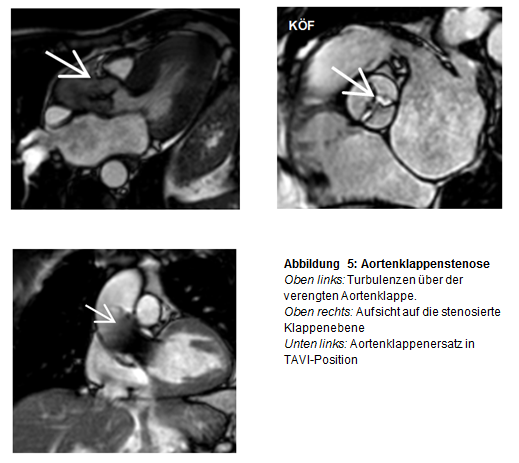

3. Strukturelle Herzerkankungen (SHD) und angeborene Herzfehler

Mit Hilfe von planimetrischen Verfahren (Bestimmung der Klappenöffnungsfläche) sowie Phasen-Kontrast-Sequenzen kann sowohl die morphologische als auch funktionelle Quantifizierung von Herzklappenerkrankungen (z.B. Aortenklappen-Erkrankungen) erfolgen. Nach erfolgter minimalinvasiver Klappenimplantation kann die Funktion der Herzklappe sowie die Struktur des Myokards verlaufsbeurteilt werden.

Vor und nach Aortenklappenersatz Darstellung großer Gefäße